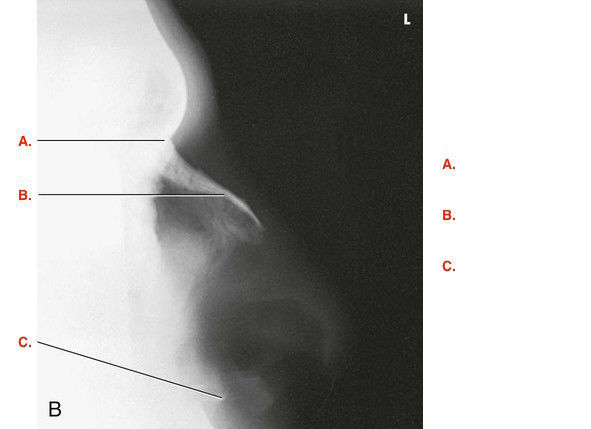

Question 5

Question

Label the image

Image:

5ce0f127-c0ff-4a4e-912e-70e533df114b (image/jpeg)

Answer

temporal process of zygoma

zygomatic arch